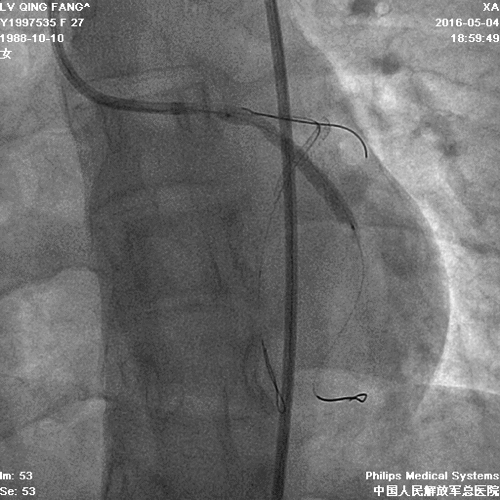

PCI